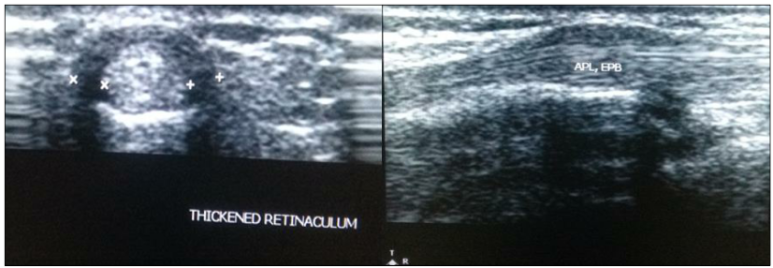

첫째,

정상적인 손목 터널 막의 두께는 얇아야 하는데,

환자들의 경우 평균

1.65mm까지 두꺼워져 있었습니다.** 심한 분은 2.22mm까지 두꺼워져 있었죠.**

터널이 두꺼워지니

힘줄이 움직일 공간이 없어 꽉 끼는 상태가 됩니다.

둘째,

놀랍게도 환자의 40%에서

하나의 방이어야 할 공간에

격막(Septum)이라는 칸막이가 존재했습니다.** 이게 왜 중요할까요?

DOI: http://dx.doi.org/10.18203/2320-6012.ijrms20173989 이 '벽'이 있으면 주사 치료를 할 때 약물이 벽에 막혀 반대편 힘줄까지 도달하지 못합니다. 직접 눈으로 보지 않고 Blind 주사를 놓으면 효과가 반감될 수밖에 없는 구조적인 이유가 있었던 겁니다. 셋째, 더 놀라운 건, 환자의 60%에서 장무지외전근(APL) 힘줄이 한 가닥이 아니라 여러 가닥(Multiple slips)으로 갈라져 있었다는 점입니다.